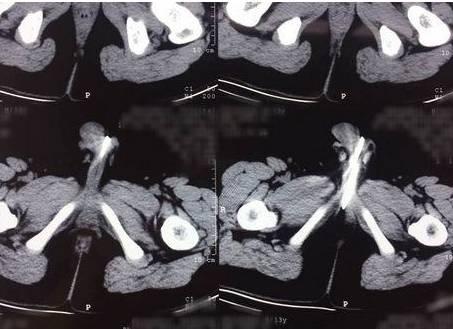

医生问家长,知道不知道那些是什么东西?家长说:”我们问了宝宝,他说是把玩具里的小磁珠塞进去了。“天啊!从X光片看来,宝宝塞了好几十颗小磁珠进去尿道里,而且有些还挺深入的,有十几颗小磁珠已经进入了膀胱,还有十来颗珠子塞在尿道口。

医生本来想用镊子伸进宝宝的尿道,把珠子夹出来,但是发现这些珠子有很强的磁性,只要镊子伸进去就会别吸住,根本没有办法把珠子从尿道夹出来。最后,医生只好想出另外一个方案,把珠子用铁丝全部往里边塞,然后把膀胱部位切开,再从膀胱里边把珠子全部夹出来。

负责做手术的王医生说:”这次的经历真让我感到很吃惊,因为切开宝宝的膀胱以后,我在前边的部位找到了十几颗珠子,还有七八颗珠子藏在宝宝的后尿道,难怪他会尿血了。如果再晚点送来医院,后果不堪设想。“